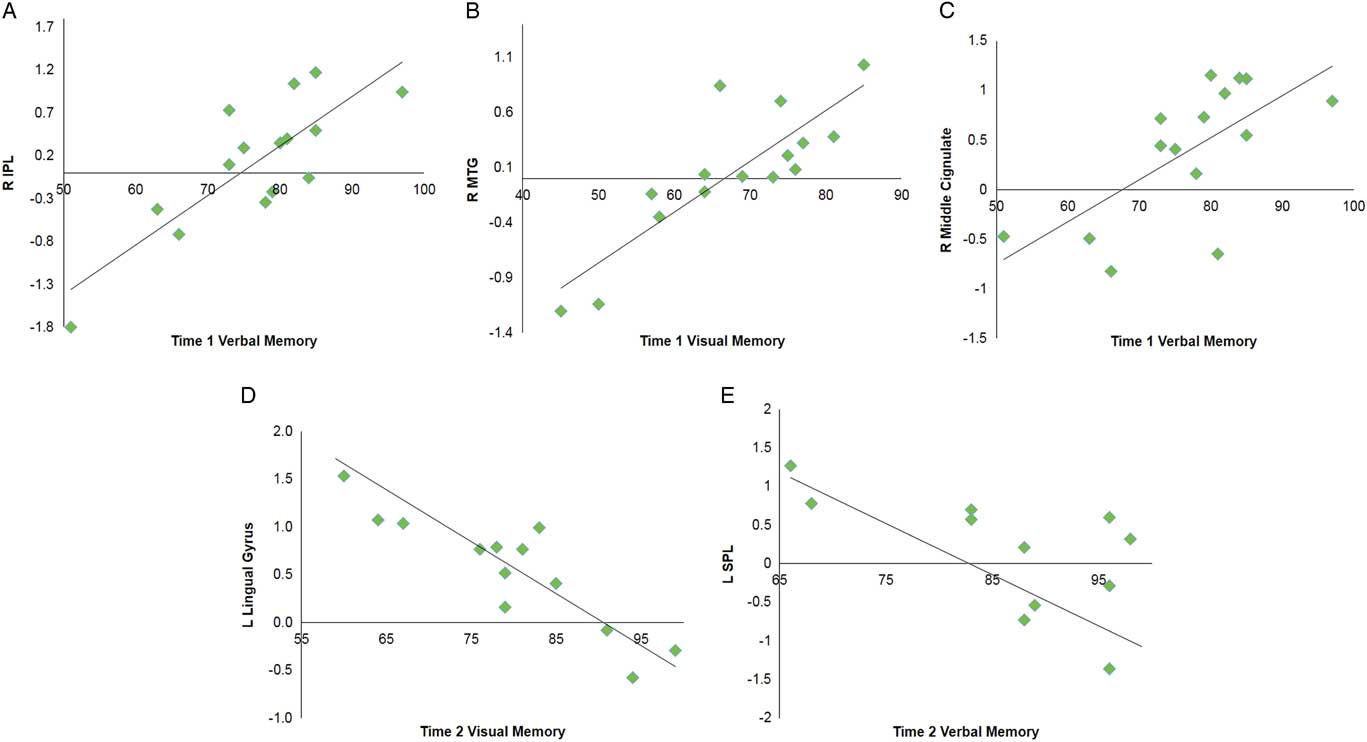

Multiple regression analyses were performed within the SRC group at time 1 and time 2 to assess correlations between functional connectivity and performance on visual and verbal memory composites of the ImPACT. At time 1, significant positive correlations were found between the DMN components and performance on verbal memory for right MCG, postcentral gyrus, and lingual gyrus, and bilateral inferior parietal lobule. A positive relationship was also found for visual memory in the right MTG. No significant negative correlations were seen at time 1. At time 2, a significant negative correlation was with verbal memory for the right vermis, left superior parietal lobule and superior frontal gyrus (SFG). A negative correlation was found with verbal memory for the right IPL. Visual memory at time 2 was also negatively correlated with the DMN components within the left lingual gyrus and right MFG (Table 4; Figure 3).

Fig. 3 Selected graphs showing correlations between select brain regions and verbal and visual memory composite scores on the ImPACT at time 1 (A–C) and time 2 (D,E). In all graphs, y-axis indicates functional connectivity Z scores for the labeled brain region, and x-axis indicates performance score on the labeled ImPACT measure, with higher scores indicative of better performance. R, right hemisphere; L, left hemisphere; IPL, inferior parietal lobule; MTG, middle temporal gyrus; SPL, superior parietal lobule.

Table 4 Multiple regression analyses within the SRC group for time 1 and time 2 separately to assess correlations between DMN component functional connectivity and performance on verbal memory and visual memory composites of the ImPACT

A positive correlation indicates better performance on ImPACT measures is associated with functional connectivity in these brain regions, and negative correlation indicates poorer performance on ImPACT measures is associated with functional connectivity in these brain regions.

L=left hemisphere; R=right hemisphere; BA=Brodmann area; MFG=middle frontal gyrus; MTG=middle temporal gyrus; IPL=inferior parietal lobule; SPL=superior parietal lobule; SFG=superior frontal gyrus.

Memory measures on the ImPACT were most sensitive to differences between adolescents with and without SRC. Particularly noteworthy are the positive correlations between the memory scores and bilateral IPL (including supramarginal gyrus) at time 1. The IPL is a well-known component of the frontal-parietal network involved in sustained attention modulation necessary for working memory (Smith & Jonides, Reference Smith and Jonides1998). Additionally, neuroimaging studies have implicated disruption of IPL in SRC (Jantzen, Anderson, Steinberg, & Kelso, Reference Jantzen, Anderson, Steinberg and Kelso2004; Keightley et al., Reference Keightley, Singh Saluja, Chen, Gagnon, Leonard, Petrides and Ptito2014). Hillary and Grafman (Reference Hillary and Grafman2017) postulate that DMN hubs, of which IPL is a primary hub (the authors use graph theory analyses and refer to hubs as “rich-club nodes”), are functionally hyperconnected to the other network regions after brain injury to overcome network disruption.

While this may be adaptive in the short-term, such as allowing the individuals with SRC to function largely within normal limits, there is likely a trade-off between excessive metabolic demand of these primary “rich-club” hubs and risk of longer-term damage to these regions (Hillary & Grafman, Reference Hillary and Grafman2017). As such, specific to our results, hyperconnectivity of the DMN regions, including IPL, at time 1 suggests an initial compensation for the SRC group to maintain memory performances. Nevertheless, the SRC group continued to remain significantly different from controls with regards to performance at time 1. At time 2, cognitive performance on the ImPACT for the SRC group was not significantly different than controls and behavioral performance in the SRC group had returned to baseline performance. Nevertheless, a positive correlation with IPL remained at time 2, suggesting that the IPL is at risk for chronic hyperactivity as it continues to compensate for network disruption of the DMN. Yet at time 2, negative correlations with both frontal (e.g., SFG, MFG) and posterior (e.g., vermis, lingual gyrus) regions were also seen.

Additionally, results correlating visual-motor coordination and rs-fMRI also fit this pattern, with precuneus, another DMN hub, differentially being recruited at time 1 and time 2. Taken together, these negative correlation findings are consistent with resource allocation theory in that those individuals with increased activity in these regions showed decreased performance on memory measures. Johnson et al. (Reference Johnson, Zhang, Gay, Horovitz, Hallett, Sebastianelli and Slobounov2012) suggested that altered resting state activity post-SRC was related to dysfunction of long-distance connections between frontal and occipital cortices as seen in other neurological and neurodevelopmental clinical populations.

As such, a subsample of our SRC group who continue to have lower performance on memory measures at time 2 may be showing altered allocation of these longer anterior to posterior functional connections. This more nuanced profile of both compensatory mechanisms (activity associated with adequate performance) and resource allocation (activity associated with impaired performance) requires further examination over time, as long-term hyperconnectivity of regions may lead to detrimental hypoconnectivity and more permanent neuropathological changes in the future (Hillary & Grafman, Reference Hillary and Grafman2017).